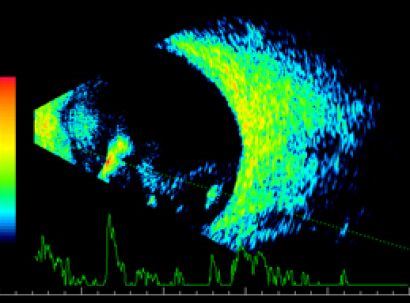

![]() |

| Тракционная отслойка сетчатки | Подвывих хрусталика |